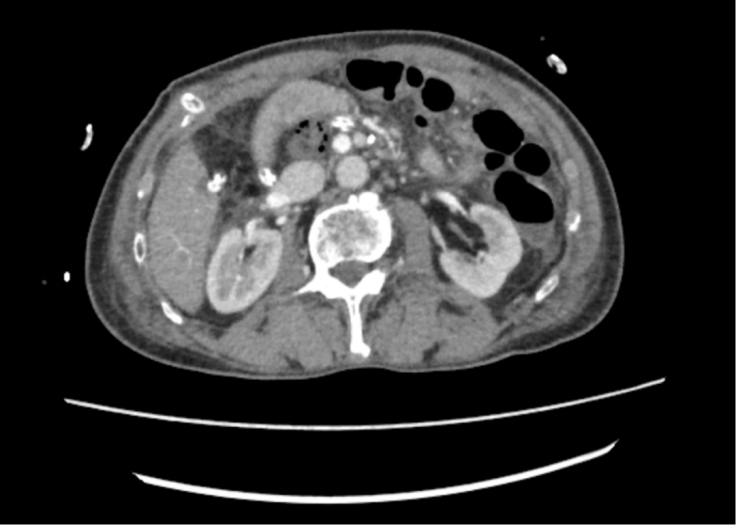

朱先生(化名)10天前突然出现身黄、目黄,小便颜色如浓茶样,前往广医五院肝胆胰外科就诊做腹部增强CT发现胰腺占位,考虑胰腺癌,肿瘤位于胰腺头部,周围环绕胆管、胃、十二指肠等重要器官,且肿瘤已累及门静脉主干,消化器官回流至肝脏的血管在此交汇,位置刁钻,手术难度极大,稍有不慎便可能引发致命性出血,风险极高。

患者术前CT(红圈内为肿瘤病灶)